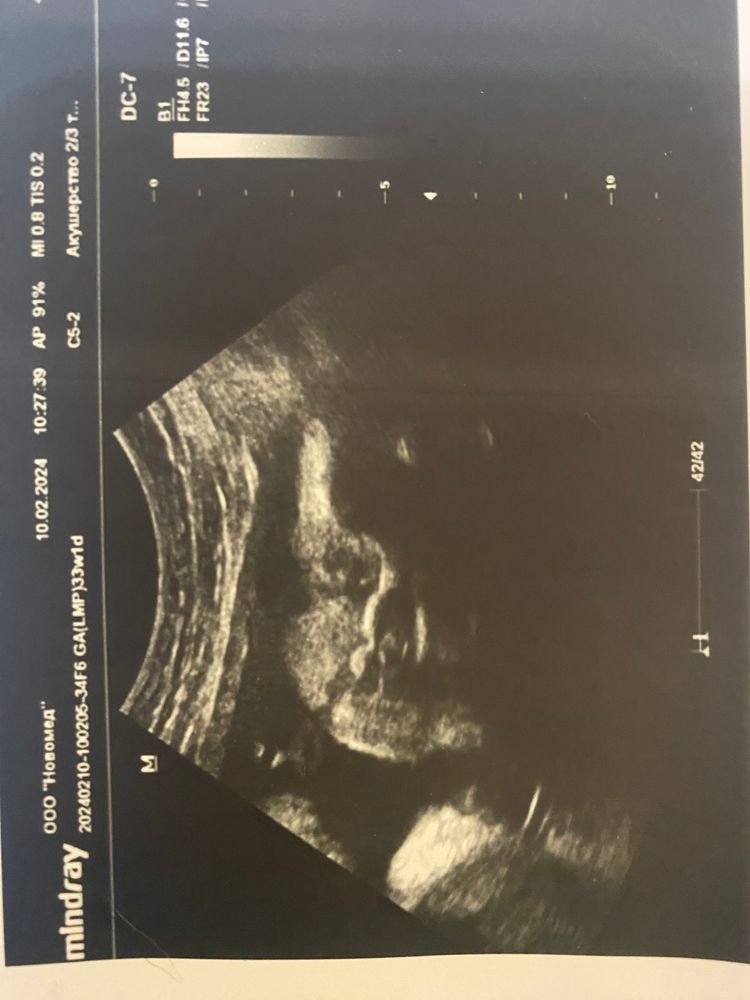

Пол малыша

Как же я мечтала о дочке💫

И вот я жду её, мою маленькую принцессу 👸